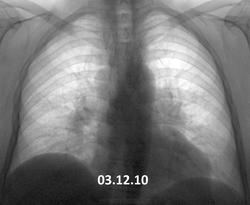

Вот такая динамика. В 2010 г. - в один день вдох-выдох- такая методика у предыдущего флюородоктора. Жалоб нет (кроме сердечных). Согласно КТ ОГК от декабря 2013 - лимфоаденопатия (как говорится - ни вашим, ни нашим). Вроде уже обращено внимание, пациент(ка) это ощутил. Успокоиться?

Отрицательная, ЛГМ? Не взирая на вдох-выдох....sad

Мне кажется, такая динамика за 3 года не впечатляет.

Нет особой разницы.

Картина одинаковая. Увеличение л/узлов средостения и лёгких. Хоть с каким диагнозом наблюдается. Сердечные проблемы здесь ни при чём, они только в ЗАГСе.

Динамики вроде нет.Похоже на саркоидоз.

Есть конечно, тот лимфоузел побольше стал. Диагноз однозначно нужно верифицировать.